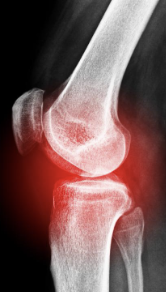

무릎 관절염 증상 원인 치료방법 알아보기

무릎 관절염 증상 원인 치료방법 등 무릎 관절염과 관련된 정보를 알아보도록 하겠습니다. 무릎 관절염은 무릎 관절의 연골이 손상되어 통증과 염증을 일으키는 질환입니다. 무릎 관절염은 나이가 들면서 자연스럽게 발생할 수도 있고, 과도한 운동이나 외상으로 인해 발생할 수도 있습니다. 무릎 관절염이 있는 사람들은 운동을 하기가 어렵고, 운동을 하지 않으면 더욱 증상이 악화될 수 있습니다. 그렇다면 무릎 관절염에 좋은 운동은 무엇일까요?